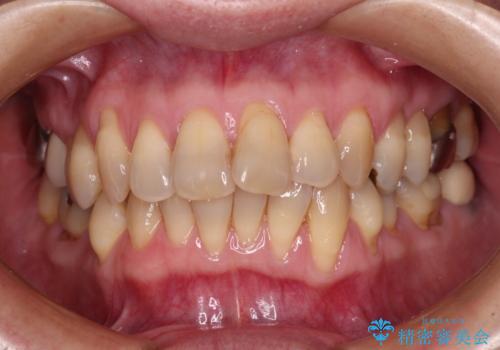

前歯のデコボコを治したい インビザラインによる矯正治療